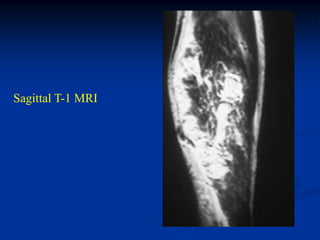

CLASSIC     Case #285         Sagittal T-1 MRI

67 year female with myxoid liposarcoma knee

Sagittal T-2 MRI

Axial T-2 MRI